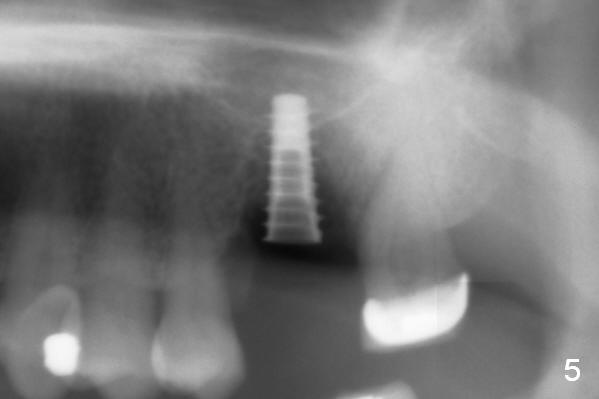

There is abundant subgingival calculus on the surfaces of the extracted tooth at #14 (Fig.1: P: palatal; MB: mesiobuccal), corresponding to the large empty socket (Fig.2 without septal bone, the buccal plate being low). Osteotomy is established palatally with Magic Expander (ME) 3.0 mm for ~ 3 mm deep (Fig.3,4) with minimal stability so that it moves during X-ray taking (Fig.4). Since the bone is dense, Magic drill 4.3 mm is used after application of ME 3.8 and 4.3 mm to complete sinus lift (Fig.5 (panoramic X-ray)). A 5x11 mm implant is placed with ~ 30 Ncm, followed by insertion of 6.5x4(3) mm Hexa abutment, bone graft and collagen membrane (Fig.6). The latter is kept in placed with an immediate provisional with clearance from the opposing dentition (Fig.7 *). Between the 1st and 3rd weeks postop, the buccal gingiva recedes with loss of bone graft (Fig.8 <) and implant thread exposure (Fig.9 * (A: abutment)). After inducing hemorrhage, allograft is placed (Fig.10 >), followed by collagen dressing (Fig.11 >). The wound closes by adding new acrylic (Fig.12 *). Thirteen days later, food is trapped in the buccal gap (Fig.13 ^). It appears that the provisional does not help wound healing. The provisional and abutment are removed; incorporating bone graft (Fig.14 *) and the implant are exposed. After placing collagen plug against the bone graft and implant, the wound is closed by periodontal dressing.